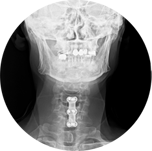

固定式的做法也稱「椎間融合術」,早期曾用自體身上取出的骨頭,但由於多了一個傷口,且取骨處疼痛目前已經幾乎沒人使用了;取而代之的是不同材質人工支架(如PEEK cage, 圖一、二)代替椎間盤,置於椎體中間。 若有頸椎脫位或穩定性不良則常需輔以鈦合金固定物(圖三、四)。 目前健保可申請的是PEEK支架,一個約三萬元左右,若申請通過時只需付十分之一的部分負擔。優點是較經濟,但缺點是須戴頸圈固定三個月,以及該節被固定融合後的頸椎間活動度會受減少。

圖三

圖四